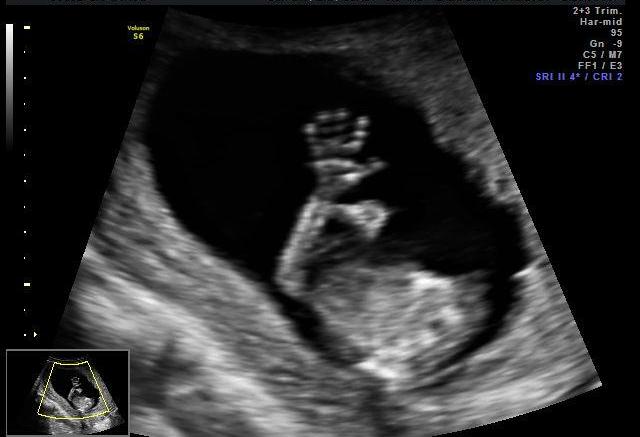

Outro momento muito marcante é entre 18 e 24 semanas de gestação, quando se começa a sentir os primeiros movimentos do bebê. A partir daí o papai pode até começar a se sentir mais participante. Se ao tocar ele ainda não sinta o bebê como a mamãe, o papai pode ouvir os movimentos, se não conseguir apenas colocando o ouvido na barriga, uma dica é usar um cone de papel. Existem aparelhos próprios para ouvir, em casa, até os batimentos cardíacos do bebê, mas para quem não quer ou não pode investir nisso, o cone de papel ajuda bastante. E além de sentir e ouvir, é muito importante tanto a mamãe quanto o papai conversarem e cantarem para o bebê para que ele se familiarize com as vozes.